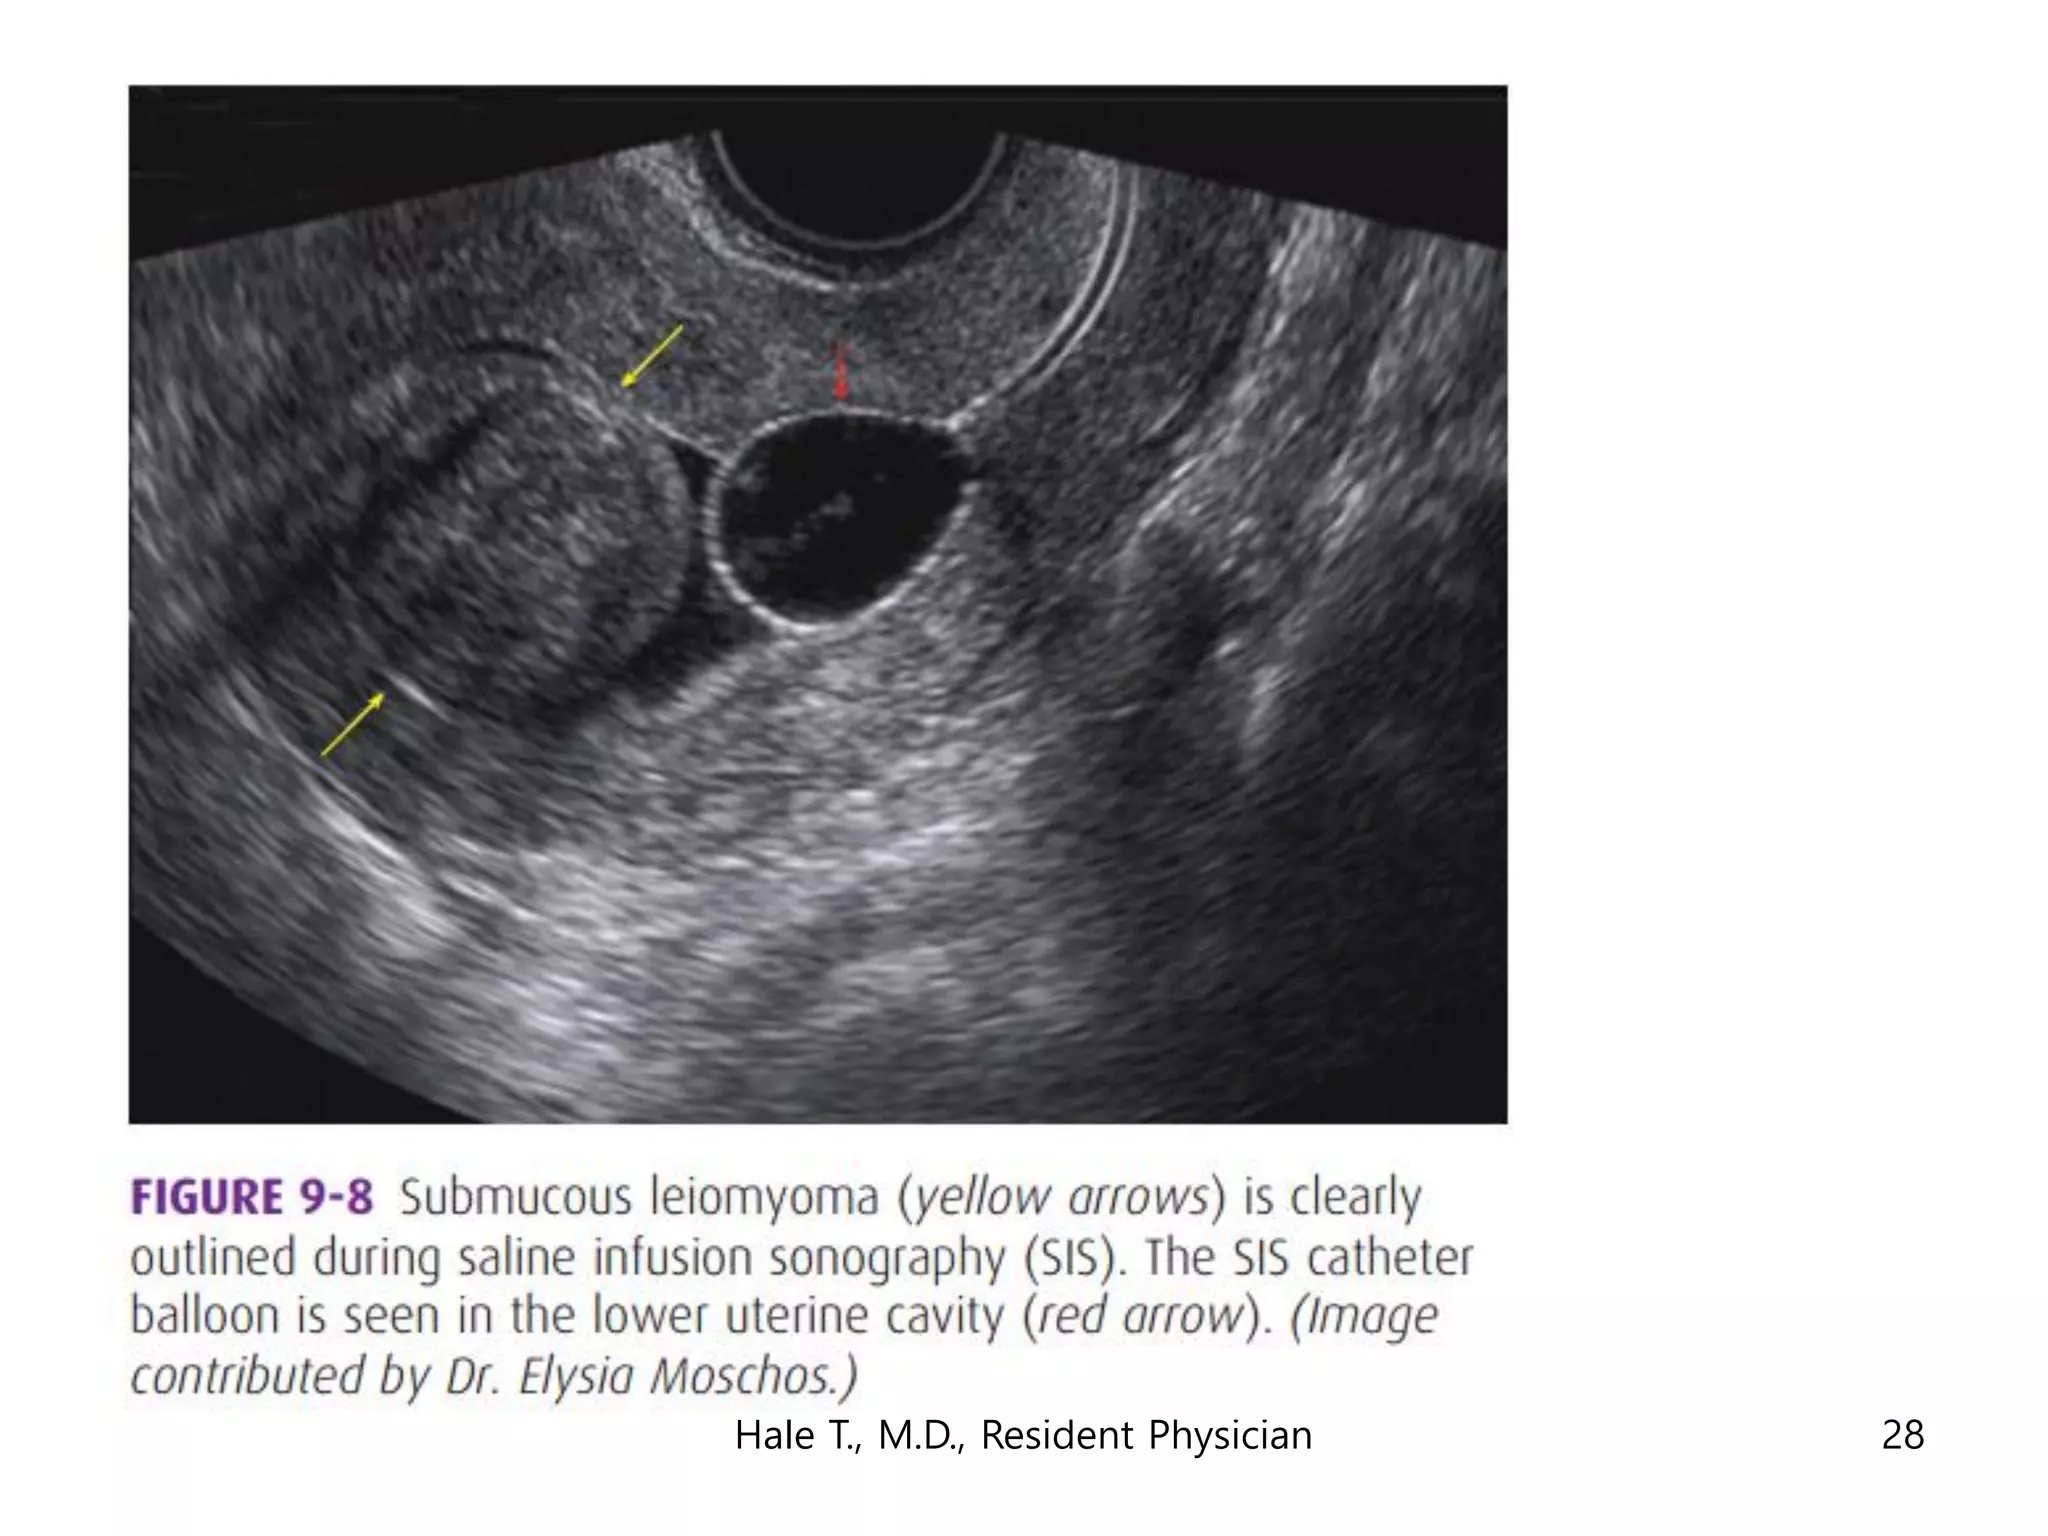

This document discusses myomas (uterine fibroids). It notes that myomas are benign smooth muscle tumors that originate in the uterus and are sensitive to estrogen and progesterone. Symptoms can include bleeding, pain, pressure, and infertility. Diagnosis is usually made through imaging like ultrasound or MRI. Treatment options include observation, drug therapy, uterine artery embolization, or surgical removal of the fibroids. The document also discusses complications that can arise if fibroids are present during pregnancy, such as pain, bleeding, preterm birth, and pregnancy loss.